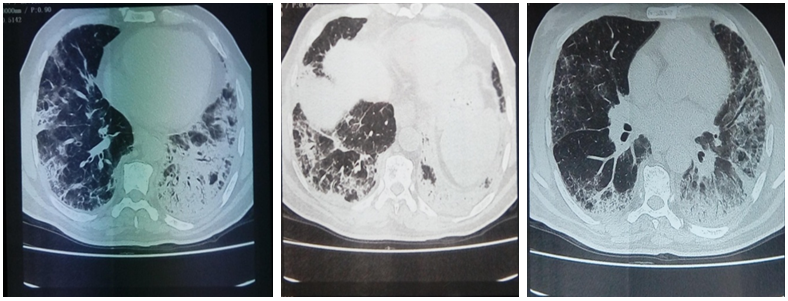

In the workup before beginning immunosuppressive treatment, a thoraco–abdomino–pelvic tomography was performed. In addition to interstitial lung disease lesions, mediastinal and hilar adenomegaly, lingular excavated lesion and confluent centrilobular micronodules of the left lung was noted (Figure 4). Rapid multiplex–PCR for Mycobacterium tuberculosis diagnosis using sputum samples was positive. The diagnosis of associated pulmonary tuberculosis was retained.

Figure 4 Chest High–resolution computed tomography showing lingular excavated lesion and confluent centrilobular micronodules of the left lung.